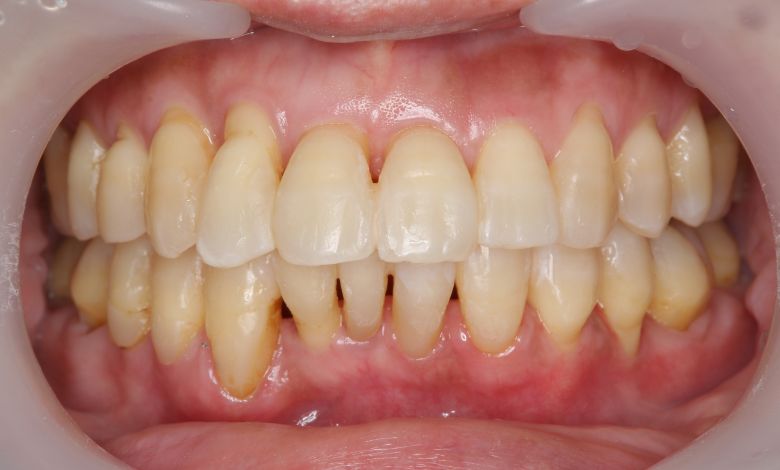

正常な咬合関係が確立され、前歯の自然なアーチと歯軸も整い、歯列全体が滑らかなカーブを描く美しい歯並びに

上下の歯がしっかりと噛み合う、美しい咬合(こうごう)が得られた

精密検査の結果、当院では抜歯を行わず、歯列弓の拡大によってスペースを確保し、非抜歯での矯正治療を選択しました。歯列の叢生(ガタガタ)は解消され、機能的かつ審美的に優れた咬合が得られました。